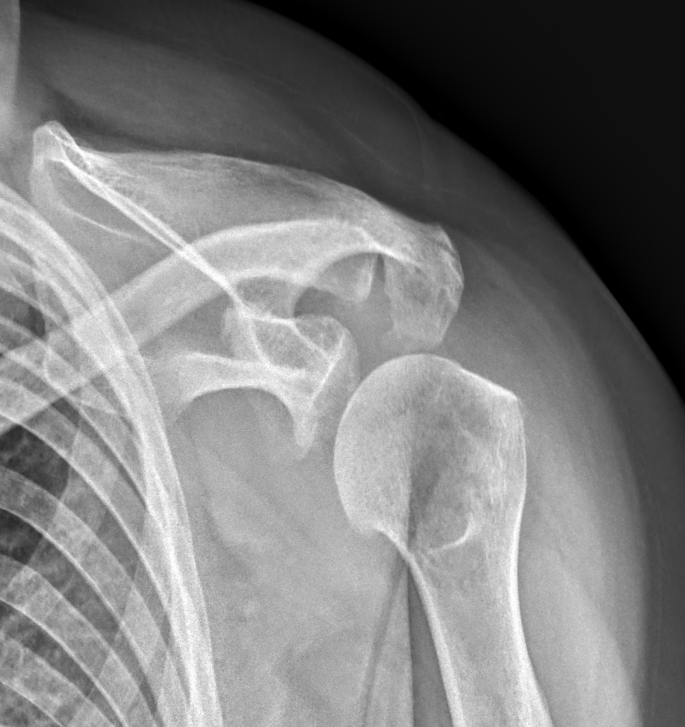

X-ray 검사 소견을 보자

어깨에는 특별한 이상 소견은 보이지 않는다.

어깨를 많이 쓰시거나 운동을 하시는 분도 아니기 때문에,

회전근개 문제일 가능성도 적다.

석회도 특별히 보이는 것은 없고 관절염 소견도 보이는 것은 없다.

경추 6-7번 사이에 유합술이 되어있다.

수술하신지는 20년 이상 지났고, 그동안은 큰 문제 없이

살아오셨다.